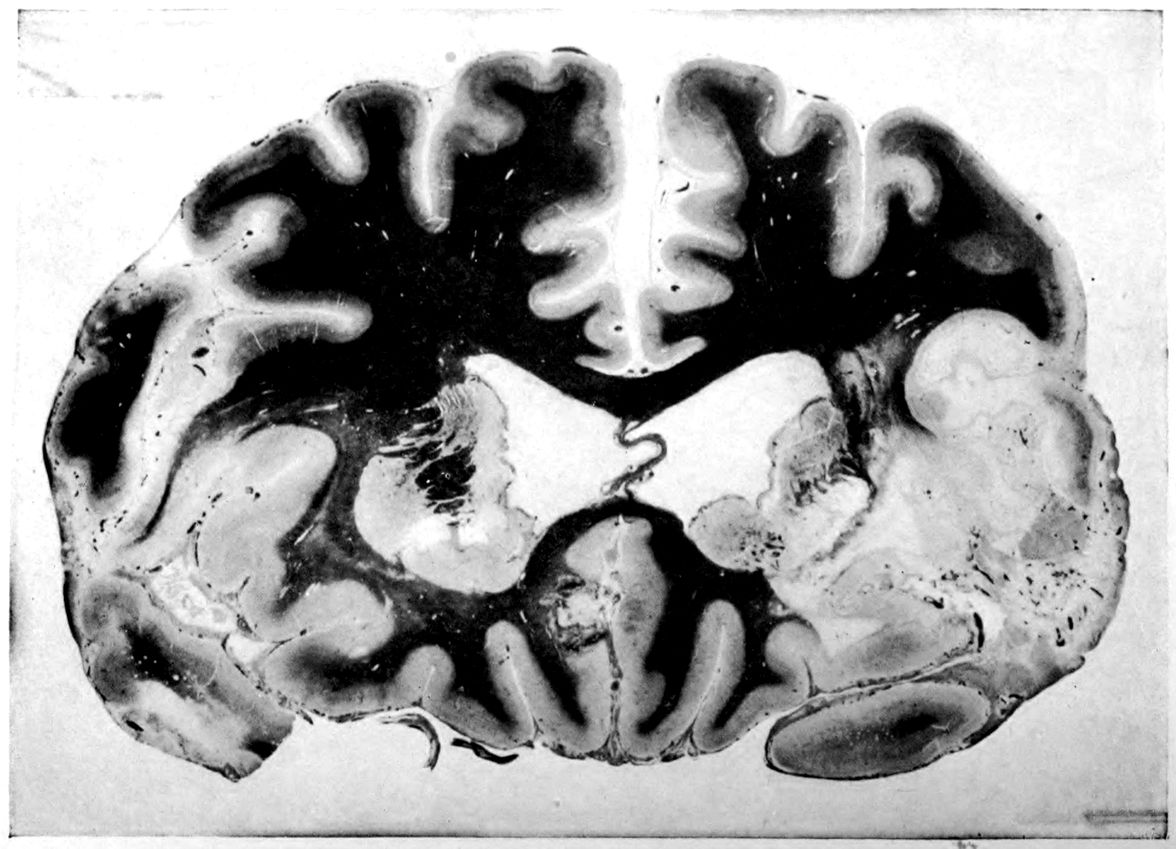

Case I. Spinal Cord (Three Levels) Showing:

A. Marginal sclerosis—effect of old meningitis now extinct.

B. Posterior column sclerosis—effect of meningitis about posterior roots also now extinct.

C. Bilateral pyramidal tract sclerosis—effect of cerebral thrombotic lesions.

Note distortion of tissues in B and C, partly artificial (tissues in places diffluent).